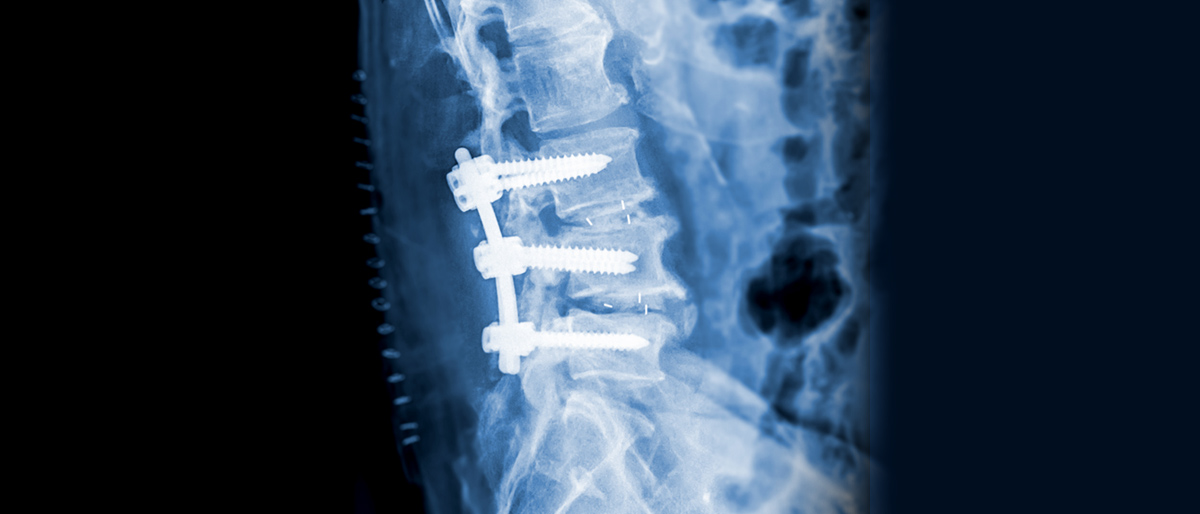

ôÃßµð½ºÅ© ¼ö¼ú À̶õ?

ôÃ߸¦ ÀÌ·ç´Â ¿©·¯ ¿ä¼ÒÀÇ ¹®Á¦·Î ôÃß°ü ¹× Ãß°£ÆÇ µî¿¡ °¡ÇÏ´Â ¼ö¼úÀû ¿ä¹ýÀ¸·Î

´ëÇ¥ÀûÀ¸·Î ÇùÂøÁõ ¼ö¼ú°ú Ãß°£ÆÇ Å»ÃâÁõ ¼ö¼úÀÌ ÀÖ½À´Ï´Ù.